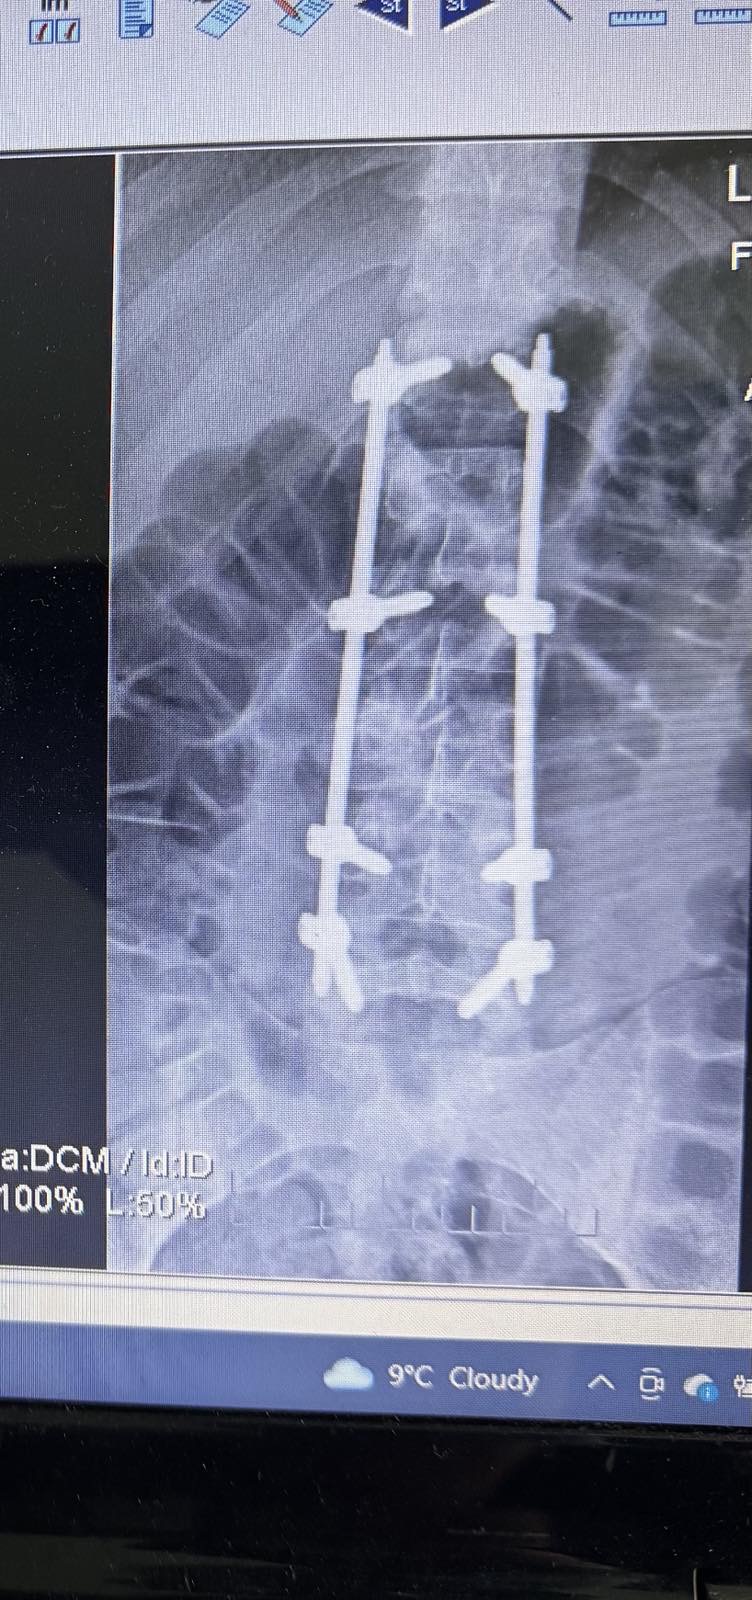

Травматологи встановили чоловіку в хребті спеціальну конструкцію

Операцію провели лікарі відділення травматології. Вони виконали транспедикулярну фіксацію хребта закритим шляхом — це малоінвазивний метод, який дозволяє стабілізувати хребет за допомогою спеціальної конструкції. За словами медиків, після операції пацієнт почувається добре та проходить реабілітацію.